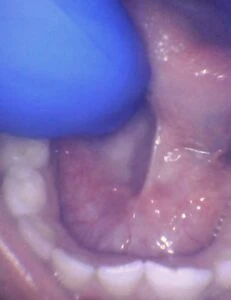

Spectrum of lip restriction in an infant

Spectrum of tongue restriction in an infant